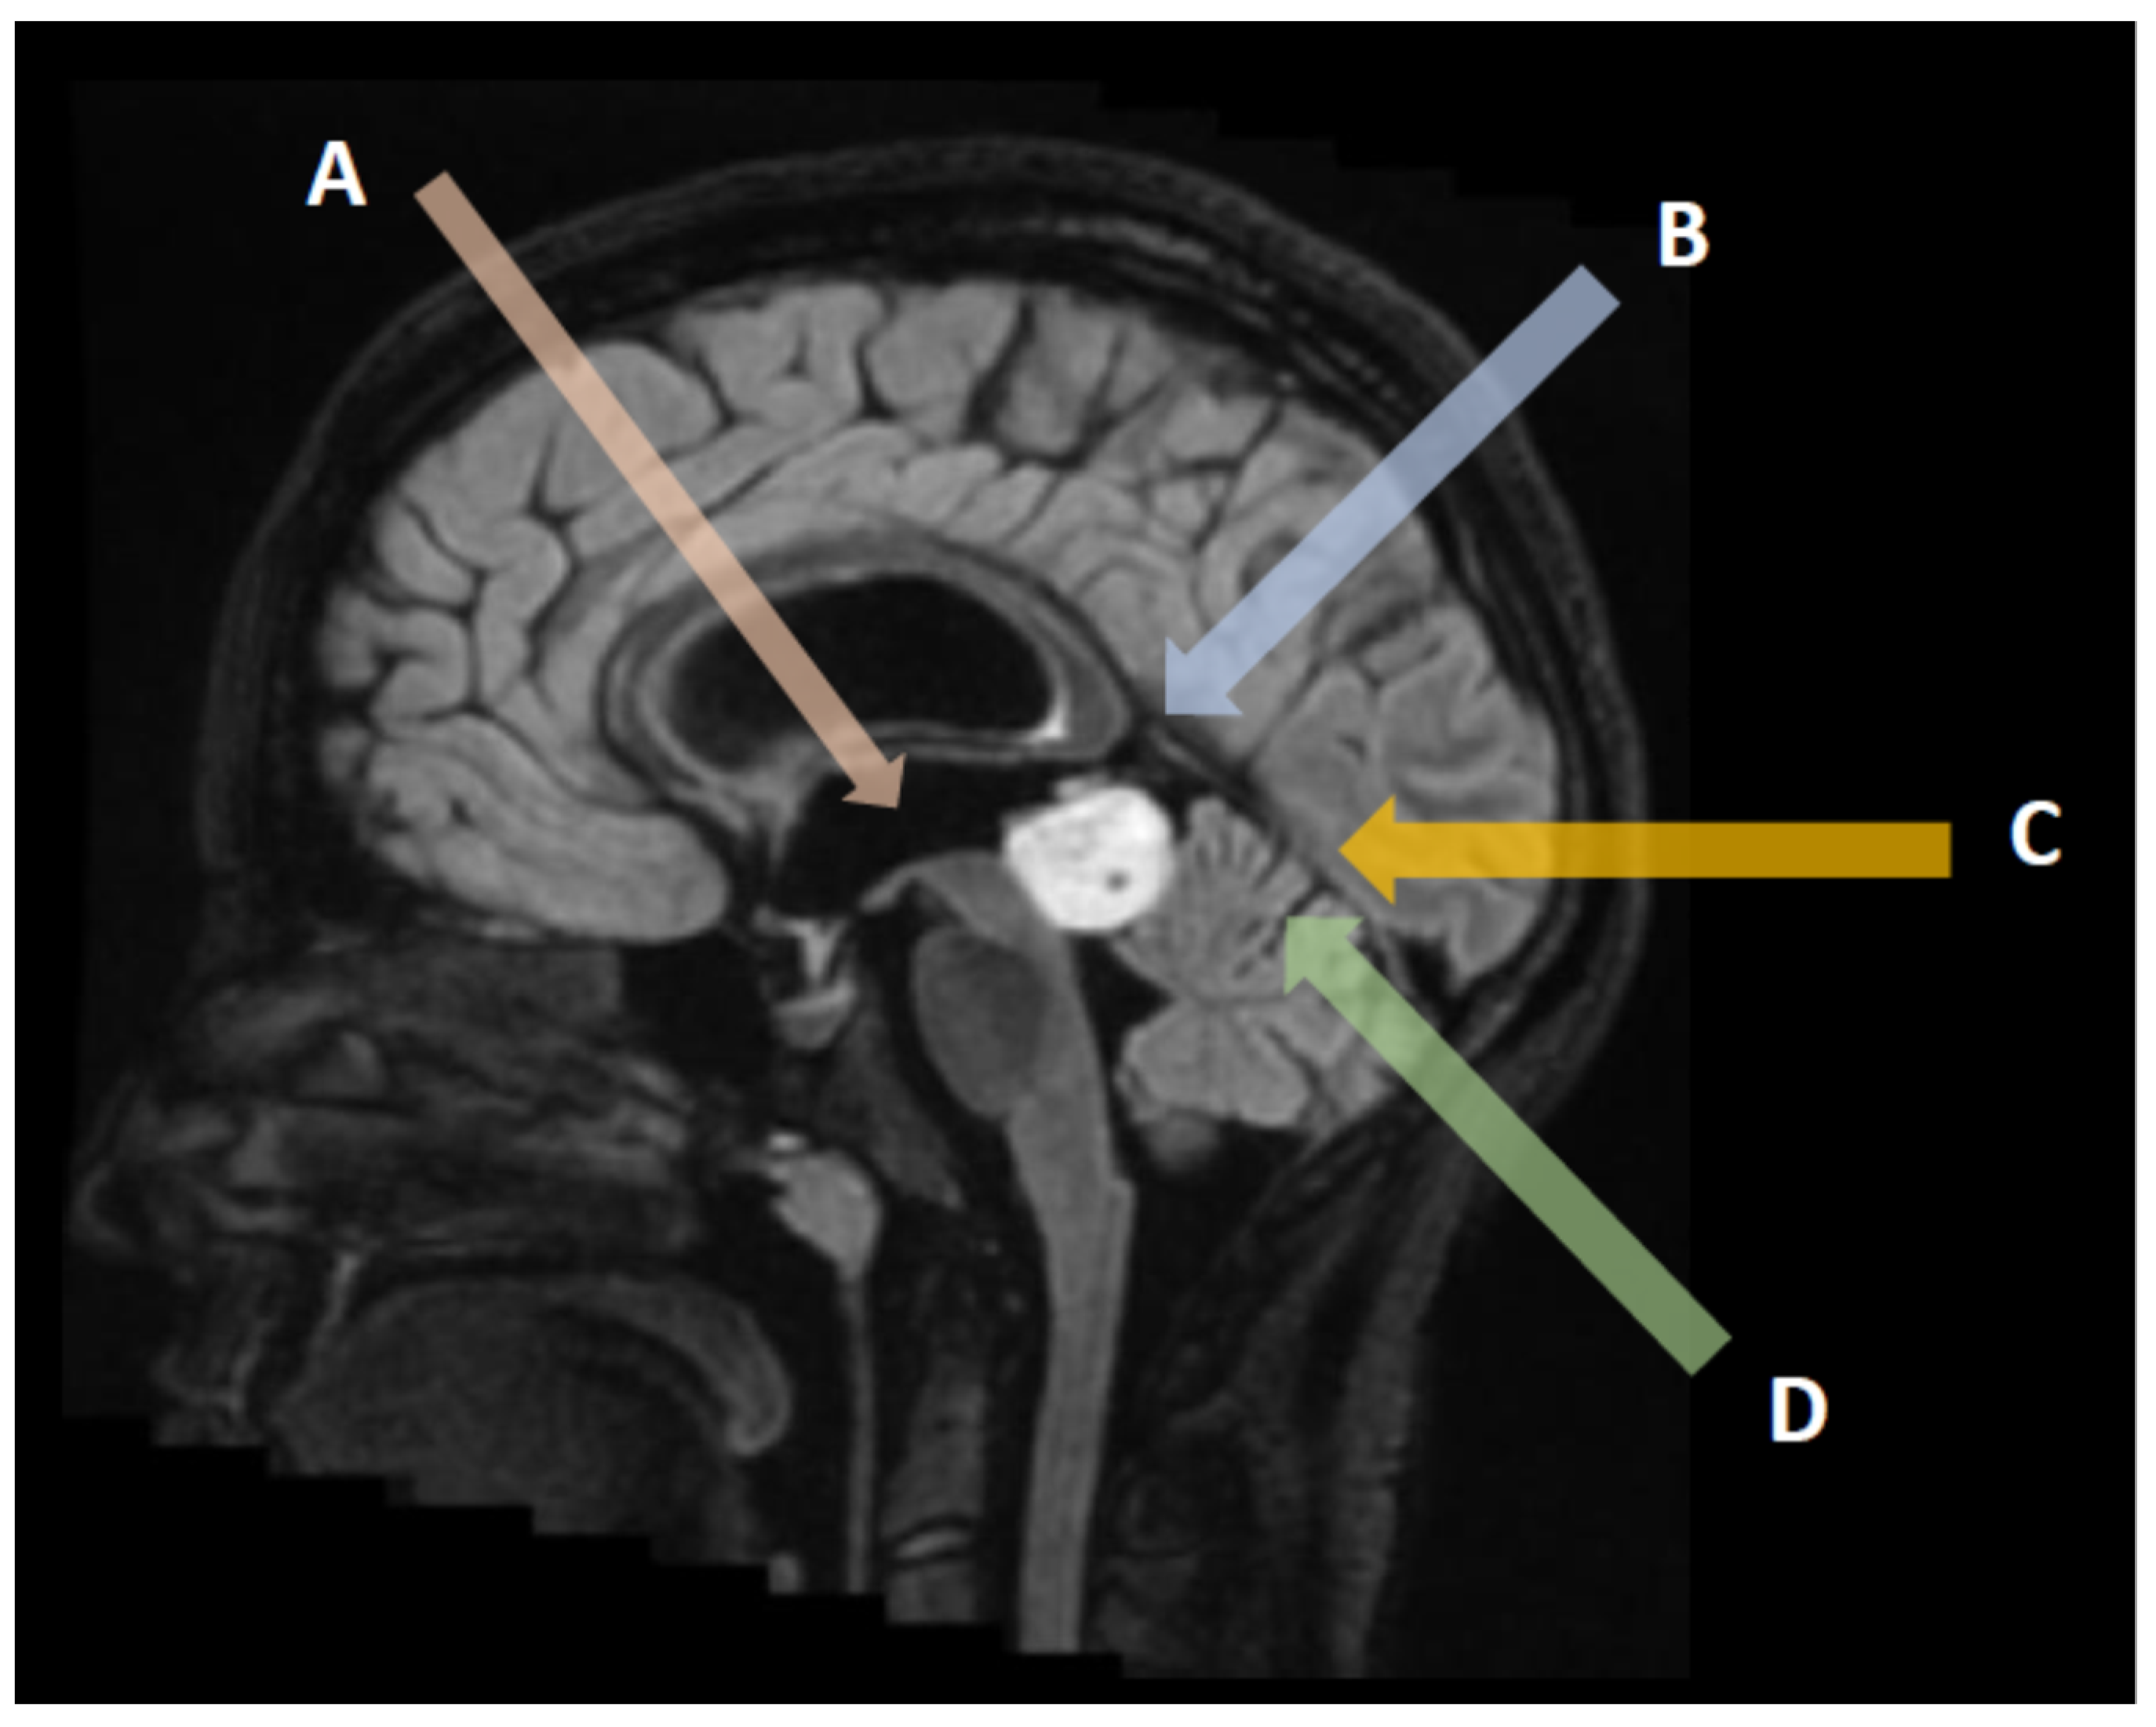

3. Neuroradiological Assessment